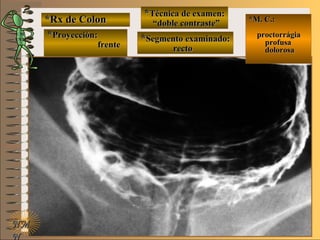

C-C-

**Segmento examinado:Segmento examinado:

*M. C.:*M. C.:

sin clínicasin clínica

NMNM

BBAA CC

E ME M

UNTUNT frentefrente

““relleno total”relleno total”

““mucosografía”mucosografía”

““doble contraste”doble contraste”

panorámicapanorámica

A-A-El examen es normal o patológico?El examen es normal o patológico?

Examen normal de estómago panorámico conExamen normal de estómago panorámico con

técnicas de : A- relleno total, B- mucosografíatécnicas de : A- relleno total, B- mucosografía

(tiene por objetivo reconocer el relieve interno(tiene por objetivo reconocer el relieve interno

grueso = a pliegues) y C- doble contraste (relievegrueso = a pliegues) y C- doble contraste (relieve

interno fino) en proyección de frenteinterno fino) en proyección de frente

B-B-Puede describir la o las imágenesPuede describir la o las imágenes

**OpciónOpción

de volverde volver

a ver lasa ver las

imágenesimágenes

En estas radiografías en proyección de frente seEn estas radiografías en proyección de frente se

deben distinguir los distintos segmentos gástricos,deben distinguir los distintos segmentos gástricos,

la distribución de los pliegues y la presencia dela distribución de los pliegues y la presencia de

áreas gástricas que nos permiten aseverar que laáreas gástricas que nos permiten aseverar que la

mucosa del estómago esta indemnemucosa del estómago esta indemne

**Opción avanzada para volver a ver las imágenes con reparosOpción avanzada para volver a ver las imágenes con reparos

D. F. M.D. F. M.